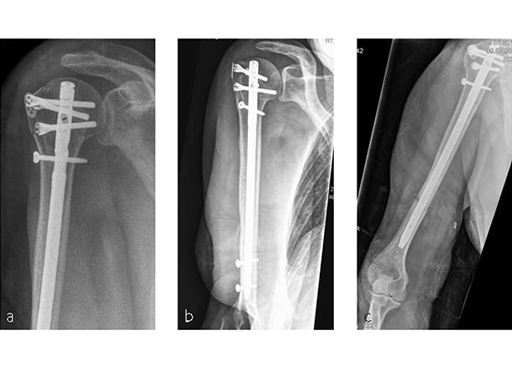

Following a fall downstairs, a 70-year-old woman sustained a head injury with intracerebral and subdural haematoma, as well as a complex fracture of the right humerus, representing a minimal displaced proximal and an oblique fracture in the distal part of the humerus (Fig 3).

After neurosurgical intervention, surgery of the humerus was planned 10 days after the index trauma. The patient was still at the neurological intensive care unit and a preoperative clinical examination of the patient, regarding radial nerve palsy, was not possible. Therefore, a surgical revision with exploration of the radial nerve and an osteosythesis of the humerus using a long MultiLoc Humeral Nail was indicated.

The patient was operated on in beach chair position. For the exploration of the radial nerve, a limited anterolateral approach was used. The nerve was mobilized and retracted laterally. An anterolateral approach to the proximal humerus was performed. The supraspinatus showed a small acute rupture without retraction. The supraspinatus tendon was split to get access to the insertion area on the humeral head. A 270 mm long MultiLock Humeral Nail of 8.5 mm diameter was inserted under visual and x-ray control to the desired endpoint. Reduction of both the proximal and the distal humerus fracture was anatomical. In the lateral view there was a small gap, and it was decided to apply compression after distal locking (Fig 4). Proximally, three MultiLoc screws were inserted and a 2 mm end cap was placed. Finally, the supraspinatus rupture was reconstructed with transosseous sutures and secured with an augmentation plate. The posterior greater tuberosity fracture was secured with Fiber Wire to the MultiLoc screws. Figure 5 illustrates the definitive fixation.